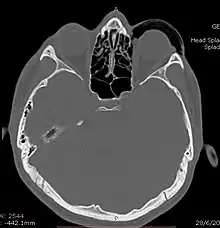

CT scan taken from the transverse plane demonstrating orbital emphysema.[39]

Computed tomography is effective and sensitive in the diagnosis of orbital emphysema,[3][37] as it can confirm the anatomical location and size of air, bony defects, indentation of the eyeball, and the condition of the optic nerve, as well as the presence of any extraocular muscle entrapment and herniation of preorbital fat into the sinus cavities.[3][15][38] The location of the orbital emphysema is present near the site of the fracture.[1][3] The scans are usually taken along the transverse plane. Transverse images allow the evaluation of fractures in medial and lateral orbital walls. By reformatting these transverse images or taking coronal images, the examination of orbital floor and roof is permitted. Helical scanning is preferred as it has a lower imaging time and radiation dose comparing to conventional scanning, especially when reforming transverse helical scans into coronal images.[3] The staging of orbital emphysema can then be determined with visual acuity examination and ophthalmoscopy.[6] A disadvantage of using a CT scan is that when detecting air after orbital trauma, the presence of a wooden foreign object can give a false positive result of orbital emphysema. The wooden object can mimic the presence of orbital emphysema. Therefore, patients’ medical history is crucial in making the correct diagnosis.[3]